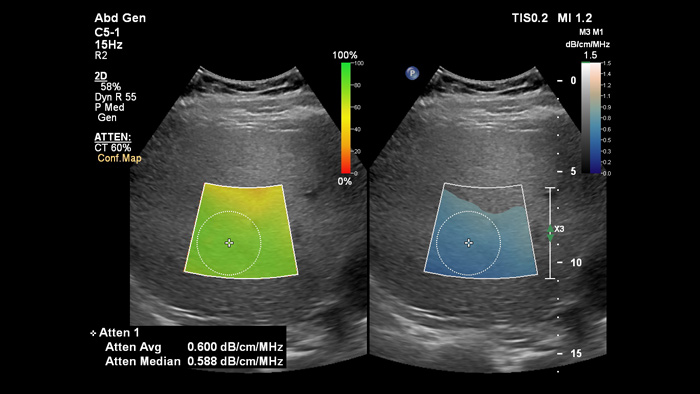

La obtención de imágenes de atenuación permite medir la cantidad de grasa presente en el hígado calculando el coeficiente de atenuación del sonido absorbido por el parénquima hepático. Este método proporciona parámetros de atenuación cuantitativos que pueden ayudar a los médicos en el tratamiento de pacientes con esteatosis hepática.

Obtención de imágenes de atenuación